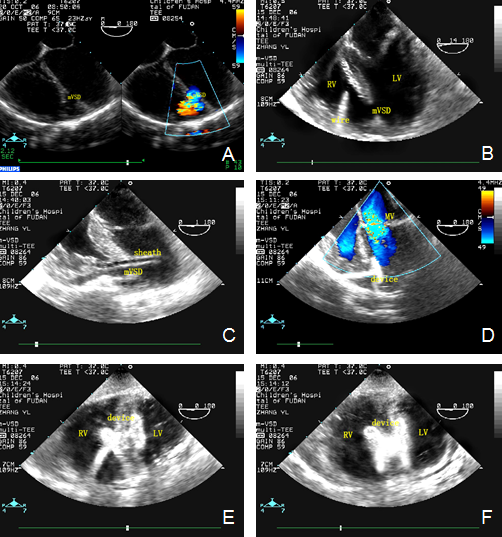

经食管超声心动图监测肌部室间隔缺损镶嵌治疗